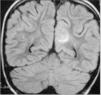

Observación ClínicaCaso 1La paciente es una niña de 7 años diagnosticada de leucemia linfoblástica aguda de alto riesgo con infiltración algodonosa en la retina en el momento del diagnóstico y normalidad del líquido cefalorraquídeo y resonancia magnética (RM) cerebral. Se inicia tratamiento con vincristina, altas dosis de metotrexato, daunorrubicina, ciclofosfamida, corticoides y triple terapia intratecal. A los 14 días apreciamos una aplasia grave medular con signos de toxicidad de grado IV en la mucosa oral, anal y vaginal, íleo paralítico con enterocolitis mucosanguinolenta y lesiones cutáneas. Comienza con deterioro neurológico progresivo, convulsiones, somnolencia y ausencia de respuesta a estímulos, con pérdida de visión. En dos ocasiones, se detecta aumento de presión arterial (PA) con cifras de 140/95. El electroencefalograma muestra ondas lentas difusas, y la RM revela áreas hiperintensas focales bilaterales, con afectación de cerebelo (figs. 1, 2 y 3). Se suspende la quimioterapia y se inicia radioterapia de globos oculares (12 Gy) y craneoespinal (18/12 Gy) por sospecha de infiltración leucémica del sistema nervioso central (SNC).

Ante la sospecha de LEPR, se deben realizar pruebas de imagen, en especial, RM ya que es la técnica radiológica más sensible para la demostración del edema cerebral y puede evidenciar lesiones pequeñas y focales no demostradas con la tomografía. Suele observarse alteraciones de la sustancia blanca supratentorial e infratentorial de límites poco definidos consecuencia del edema cerebral. También puede verse afectación cortical con borrado de surcos y alteraciones en otras zonas, como la afectación cerebelosa de nuestra primera paciente. La RM mostraría en secuencias T1 una señal hipointensa, y en T2, FLAIR y densidad protónica, hiperintensa. Deben incluirse imágenes de difusión de la RM, interesantes desde el punto de vista diagnóstico, pero sobre todo pronóstico, que permite distinguir el edema vasogénico del citotóxico. El edema vasogénico en región posterior es la anormalidad de imagen clásicamente descrita y se asocia a un proceso reversible con pronóstico favorable por lesiones isquémicas precoces. En contraste, la progresión del edema vasogénico a citotóxico es un hallazgo atípico e indicativo de irreversibilidad, ya que implica conversión a infarto e incluso hemorragia cerebral2,14.